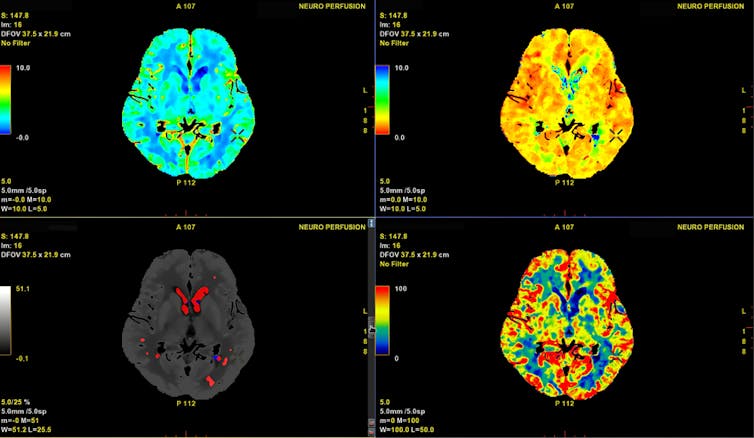

Ainsi, il existe un engouement neurophile qui rend crédule. Il repose sur l’intuition (erronée) que l’imagerie cérébrale a systématiquement valeur probante et permet d’observer objectivement un processus de pensée – un peu comme l’observation d’une radio permet de déceler la présence ou non d’une fracture.

Or, en réalité, les données d’imagerie sont le résultat d’analyses statistiques complexes et ne sont pas moins sujettes à interprétation que les données issues, par exemple, de la génétique ou de l’observation des comportements. Et l’allure séduisante de l’imagerie cérébrale joue des tours à notre esprit : il a même été montré que le simple fait d’accompagner un texte d’une image de cerveau augmente l’impression de véracité du propos qui l’accompagne, y compris lorsque celui-ci comporte des erreurs de logique évidentes.